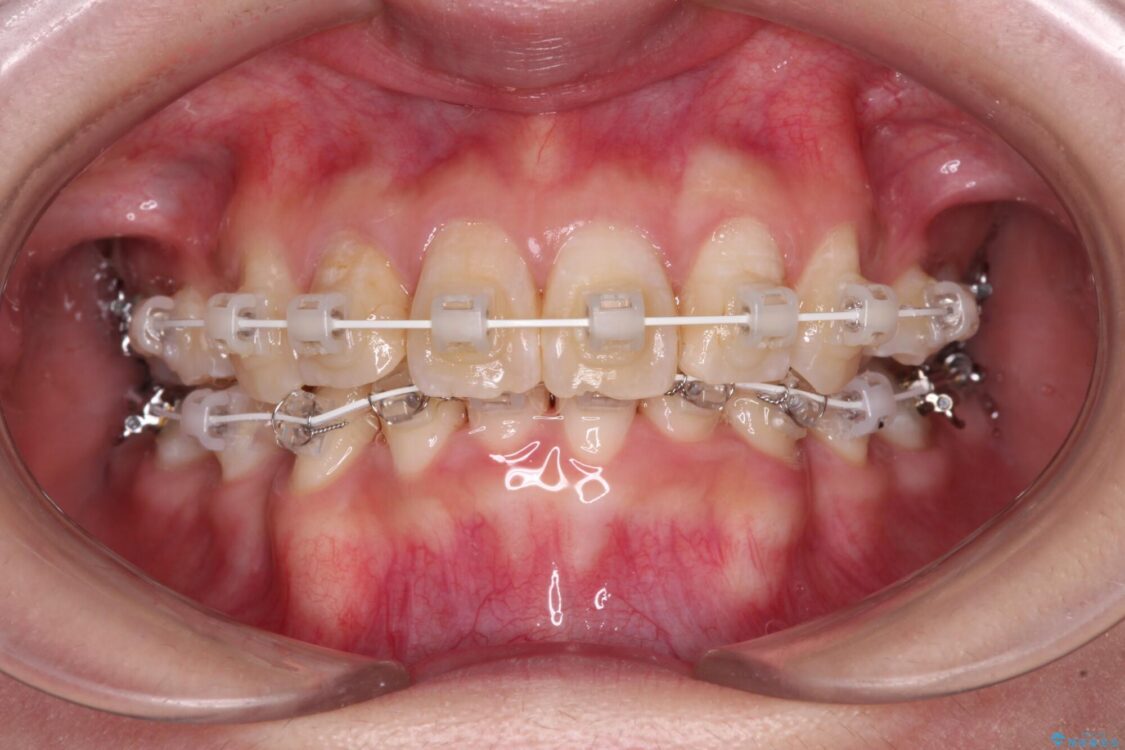

治療途中

• デコボコと深い咬み合わせ ワイヤー装置での抜歯矯正 治療途中画像

咬み合わせが深く、そのままでは上顎の抜歯スペースが閉じきらない可能性があったため、治療初期から深い咬み合わせを改善させるように試みました。

実際にはなかなか改善されず、当初予定よりも治療期間がやや長期化してしまいました。